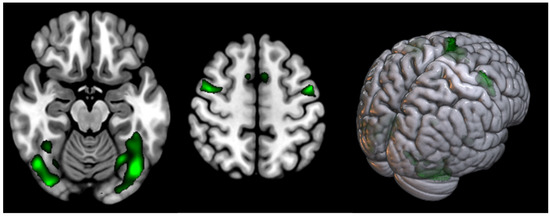

| T | Puncorr | Number of Voxels | Peak MNI Coordinate | |

|---|---|---|---|---|

| Posterior cingulate cortex (L) | 4.06 | <0.000 | 14 | −12 −42 28 |

| Posterior cingulate cortex (R) | 3.32 | 0.001 | 2 | 6 −44 50 |

| Supramarginal gyrus (L) | 3.37 | <0.000 | 23 | −38 −54 30 |

| Supramarginal gyrus (R) | 3.49 | <0.000 | 22 | 52 −50 22 |

| Opercular part of Precentral gyrus (L) | 3.77 | <0.000 | 12 | −46 8 8 |

| Opercular part of Precentral gyrus (R) | 3.47 | 0.001 | 11 | 48 4 10 |

| Cerebellum Posterior Lobe (8) (L) | 3.33 | 0.001 | 67 | −18 −68 −42 |

| Cerebellum Posterior Lobe (8) (R) | 3.25 | 0.001 | 34 | 18 −70 44 |